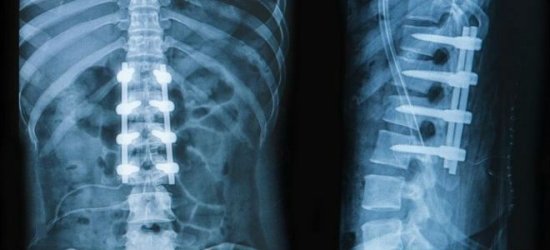

Переломы и ушибы

В результате переломов позвонков и других серьёзных травм позвоночного столба, спина внизу поясницы начинает усиленно болеть из-за того, что скелет ослаблен после травмы.

При переломе позвонков может наблюдаться сильнейшая боль в спине в целом, при локализации в левую или в правую части спины, или в конечности конечности. Если даже слабо надавить на позвоночник, то болевые ощущения серьёзно усилятся.

Типичные симптомы перелома позвонков:

- ограничение подвижности тела;

- снижение чувствительности, онемение рук и ног;

- мгновенное усиление болей при малейшем воздействии на позвонки;

- появление сильной утомляемости;

- появление одышки.

После обращения к травматологу потребуются лабораторные и аппаратные исследования, включающие в себя: анализ мочи и крови, рентгенографию, МРТ, электрокардиограмму . При лечении применяются как классические методы (фиксация и восстановление повреждённого позвонка), так и хирургические.

В качестве последствий травмы необходимо отметить запрет на тяжёлые физические нагрузки, обязательные профилактические осмотры у травматолога, проведение рентгенов. Запрет на физические нагрузки особенно важен, так как в ходе развития проблемы могут возникнуть осложнения, и боль из спинно-поясничной области может передаться в конечности.